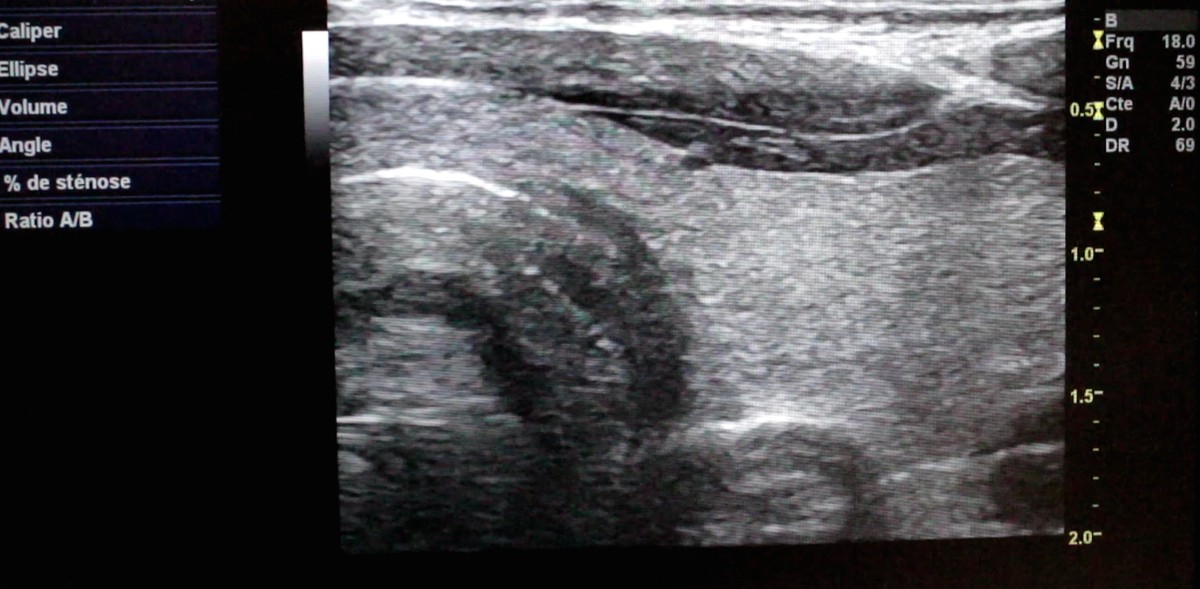

A travers ce film, j’ai voulu trouver, interroger ce dédoublement, en détournant les images médicales de leur usage initial. Grâce à la kinésiologie, j’expérimente un rapport différent au corps, mettant sa propre vie en évidence.

L’expérience de cette réalisation montre de façon saisissante l’intériorité du corps comme un environnement proche de la mer. L’eau offre une vaste gamme d’expressions.

Mon travail consiste à explorer la notion de dédoublement, les relations entre corps et esprit, en évoquant la sensation et la mémoire du corps. À travers le grossissement visuel de détails du corps, la texture, le contraste des images corporelles, l'association et la fusion d'images et le langage d'expression corporelle, cette recherche fait apparaître des problèmes d'intérêt immédiat.

Un grand merci à Gao Bo, au docteur François Lapeyre et l’équipe de l’Imagerie Paris Nord, Sarcelles, les Kinésiologues Delphine Gallien, Ana Delaperrière, Jean-Luc Penet, mes amis à Taiwan.